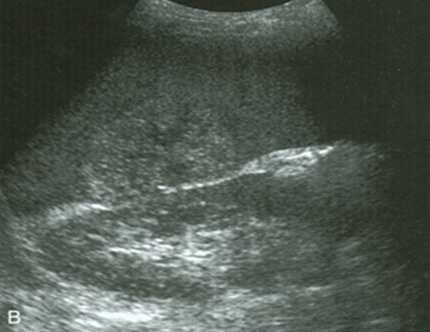

Разрыв паренхимы с более поздним разрывом капсулы - (латентный) двухмоментный разрыв селезенки. При повреждении паренхимы образуется подкапсульная или центральная гематома. Кровоизлияния в брюшную полость не происходит. В дальнейшем при физическом напряжении, происходит разрыв капсулы и возникает кровотечение в брюшную полость.

Разрыв паренхимы и капсулы с самостоятельной тампонадой - позднее свободное кровотечение - мнимый (ложный) двухмоментный разрыв селезенки. Разрыв капсулы покрывается сгустком крови или сальником, создавая временную задержку кровотечения в брюшную полость. При повышении давления в селезенке, сгусток крови отходит и неожиданно возникает кровотечение.